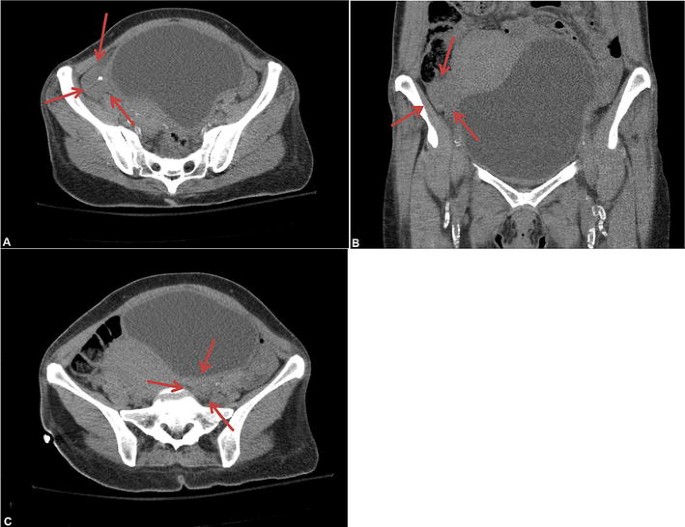

If the ovaries are not visualized, a doctor may order an ultrasound to get a better view of the ovaries. An ultrasound can help the doctor to identify any abnormalities in the ovaries, such as cysts or tumors. The ultrasound may also help to identify the cause of the non-visualization, such as endometriosis or adhesions.

In some cases, the ovaries may be too small to be seen, or they may be hidden behind other structures in the pelvis, such as the uterus or bowel. If this is the case, a different type of scan, such as an MRI or CT scan, may be required to view the ovaries.